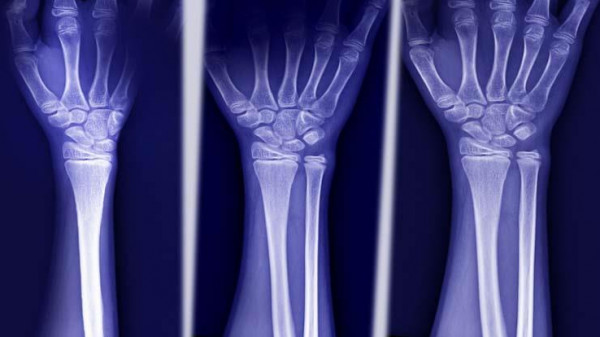

4. عظام غير قابلة للكسر

أمر لا يصدق، ولكن هناك عائلة في الولايات المتحدة ليس لدى أفرادها تاريخ من كسور العظام على الإطلاق.

وفقًا لبحث، يمكن تفسير ذلك من خلال طفرة جينية تسبب ارتفاع كثافة العظام. وفي الواقع، هذه العائلة لديها على الأرجح أقوى عظام أي شخص على الكوكب بأكمله.